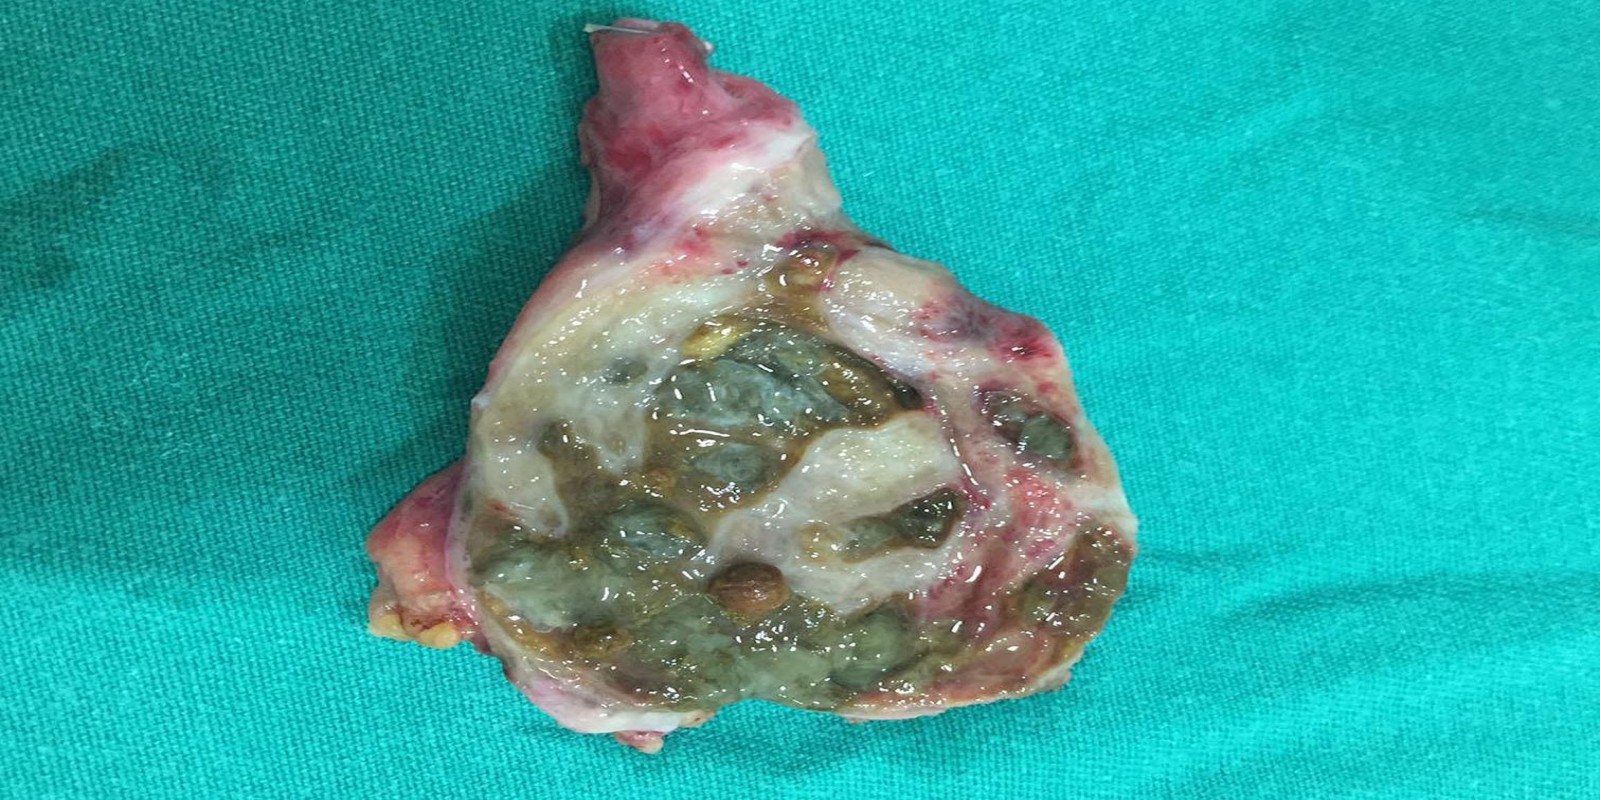

Caso Código 125B de Colecistite Aguda

Cod.: 125B